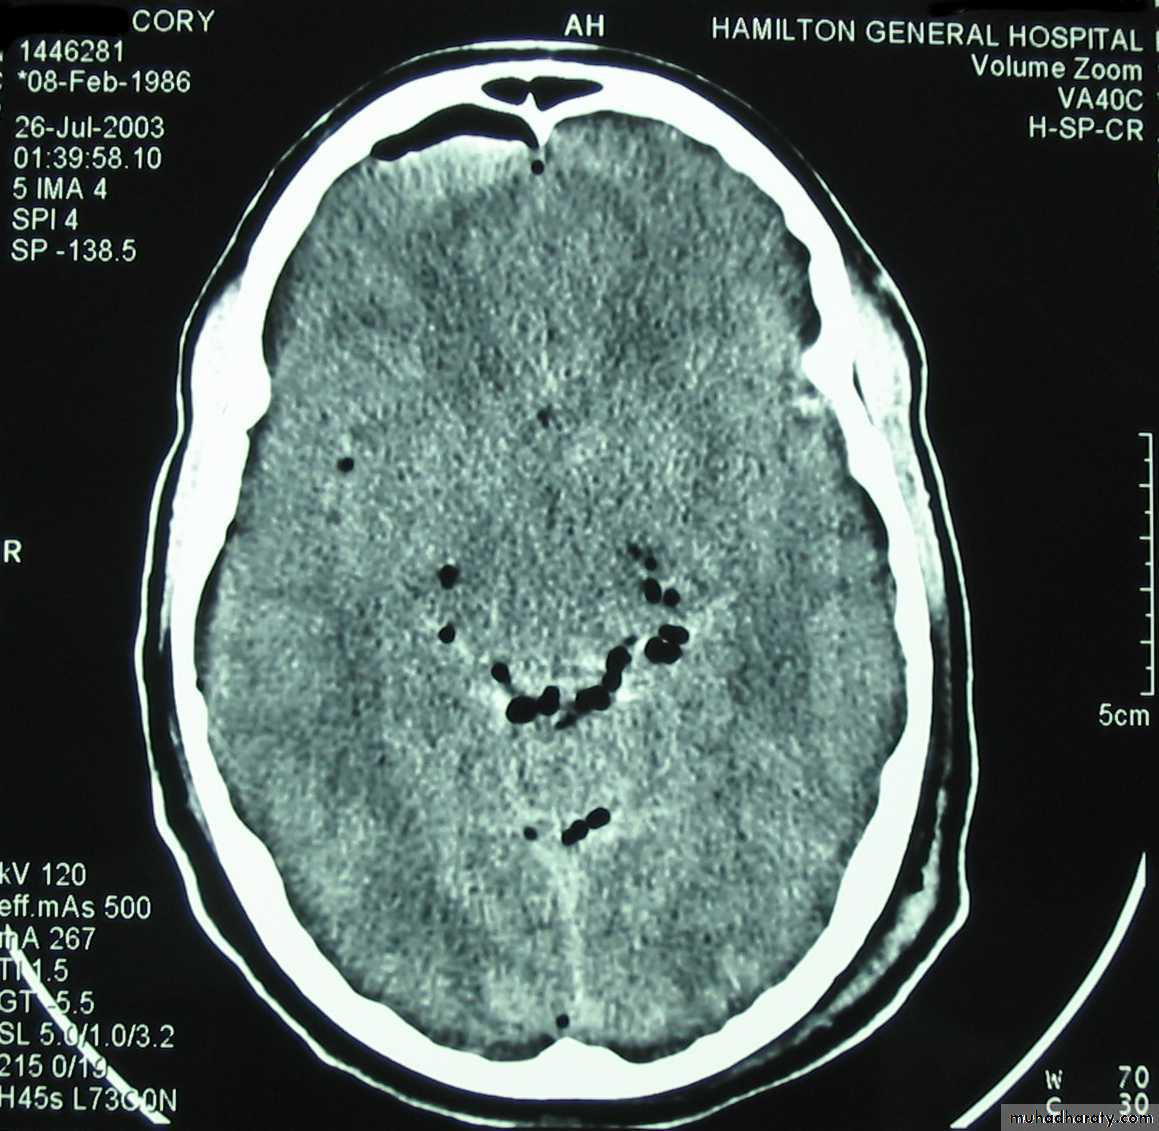

D. Intraventricular Hemorrhage:

• Blood filling ventricle (usually due to a blunt injury).• Treatment is conservative.